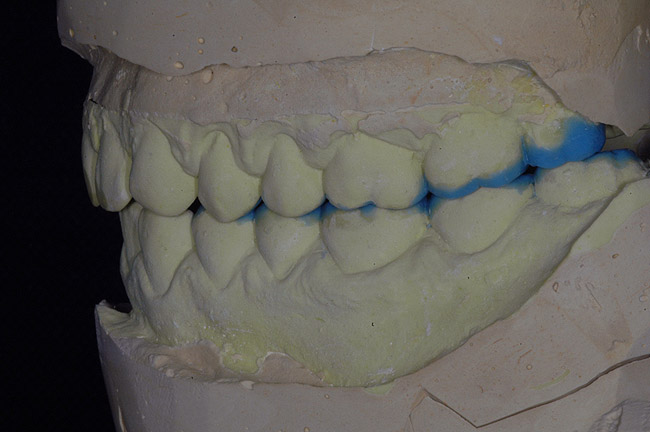

După tratamentul cauzelor GERD, s-au înregistrat amprente din alginat iar modelele din gips rezultate au fost montate pe un articulator semiajustabil. Ariile ce urmau a fi restaurate au fost modelate din ceară, pentru analiza diagnostică a relaţiei ocluzale dorite. Apoi s-a creat o lingură semirigidă din acetat pentru a servi ca şablon în timpul procedurii restauratoare. Potrivit analizei modelelor montate în articulator, înălţimea minimă pentru restabilirea dimensiunii verticale de ocluzie era de 1,5mm (fig. 4).

Opţiunea unui sistem adeziv autogravant se bazează pe absenţa etapelor de clătire şi uscare pentru menţinerea umidităţii ideale a dentinei. Sistemul adeziv folosit este clasificat ca adeziv uşor autogravant, care poate demineraliza dentina, menţinând hidroxiapatita reziduală. Acesta este considerat un avantaj pentru o mai bună adeziune şi durabilitate a restaurării.18 Totuşi, s-a propus ca demineralizarea suplimentară să fie efectuată numai pe smalţ la utilizarea acestui tip de sistem adeziv, datorită ratei sale de demineralizare mai slabe, comparativ cu acidul fosforic pentru acest substrat.18 La analiza ocluziei şi a modelelor, s-a observat lipsa spaţiului, care a fost cauzată probabil de o erupţie secundară a dinţilor pentru a compensa uzura.1,19